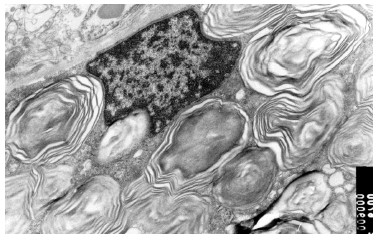

Se realizó una biopsia de una de las lesiones cutáneas cuyo estudio histológico mostró la presencia de vasos dilatados en el plexo vascular superficial de la dermis papilar. A mayor aumento se observaban abundantes vacuolas en el citoplasma de las células endoteliales (fig. 4). Todos estos hallazgos eran compatibles con angioqueratoma corporis diffusum. Se realizó un estudio analítico con hemograma y bioquímica, que incluyó las funciones renal y hepática, con valores dentro de los límites normales. Se evaluaron, además, los oligosacáridos en la orina que resultaron normales y se descartaron las glucoproteinosis (α y β -manosidosis, fucosidosis, aspartilglucosaminuria y sialidosis), gangliosidosis GM1 tipo 1, gangliosidosis GM2 tipo Sandhoff, galactosialidosis, enfermedad de Schindler y glucogenosis II, III y VI. El análisis enzimático en fibroblastos mostró unos valores normales para β -galactosidasa, hexosaminidasa y N-acetilneuraminidasa, con valores claramente disminuidos para α -galactosidasa (3,2 nmol/h/mg prot. frente a 56,5 del control), por lo que fue diagnosticado de enfermedad de Fabry. La madre del paciente presentaba unos valores en el rango de portadora (162 nmol/min/g de prot. frente a 1.144 del control). El análisis genético confirmó el estado de portadora y por lo tanto la heterozigosidad para esta enfermedad. Se practicó una biopsia renal cuyos hallazgos fueron compatibles a los referidos en la enfermedad de Fabry (fig. 5).

Fig. 4.--Detalle anatomopatológico de las lesiones cutáneas que muestra vasos dilatados en el plexo vascular superficial. (Hematoxilina-eosina, x20.)

Fig. 5.--Imagen de microscopia electrónica de biopsia renal de la madre del paciente. Depósito de globotriaosilceramida renal.